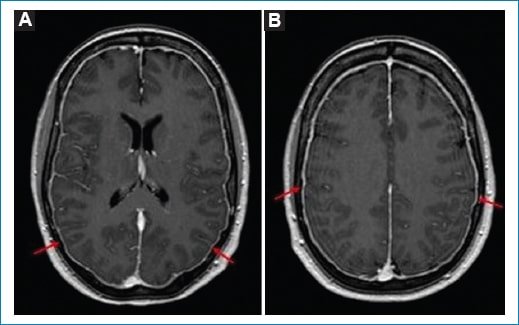

• RM: es el método de elección. Se observan engrosamiento y realce difuso dural en el 85% de los casos (Fig. 6), que puede asociarse a colección subdural, descenso de las amígdalas cerebelosas y con menor frecuencia a signos de ingurgitación venosa4,11.

Figura 6. Cefalea pospunción. Cortes axiales de RM a nivel de los ventrículos laterales (A) y los centros semiovales (B), secuencia ponderada en T1 con gadolinio. Las flechas señalan un ligero engrosamiento y realce paquimeníngeo.